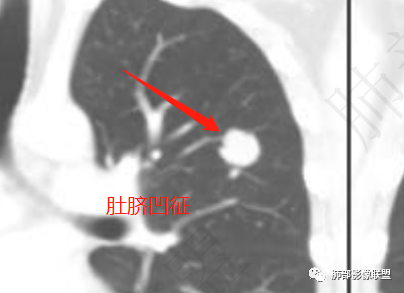

左肺上叶结节病灶,边缘光滑,有脐凹征,半年复查增大,持续强化,密度不均,内见低密度影,低密度好像是脂肪,所以考虑良性病灶,错构瘤>psp。鉴别腺癌(脐凹征有点不放心)。

1、考虑恶性病变的征象:肚脐凹征、轻度分叶征、V征或支气管半进入征、远端局部阻塞性改变,以及递增性强化等征象,临床上半年结节有增大,腺癌可以考虑;

2、考虑良性结节:可见切面征,形态较为规则,整体类圆形改变,可考虑炎性假瘤,半年后无炎性纤维组织的收缩、尖角或桃尖征改变,尤其半年后体积增大的炎性病变,还是罕见。部分层面见血管贴边征,PSP可以考虑。